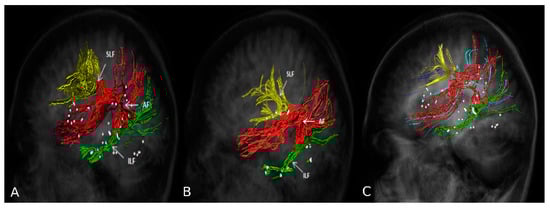

2.6. nTMS Based DTI-FT of Language Pathway

2.7. Presurgical Planning